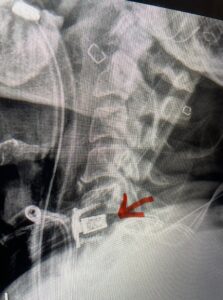

Fig 6: Intraoperative lateral cervical x-ray demonstrating placement of interbody cages and plates